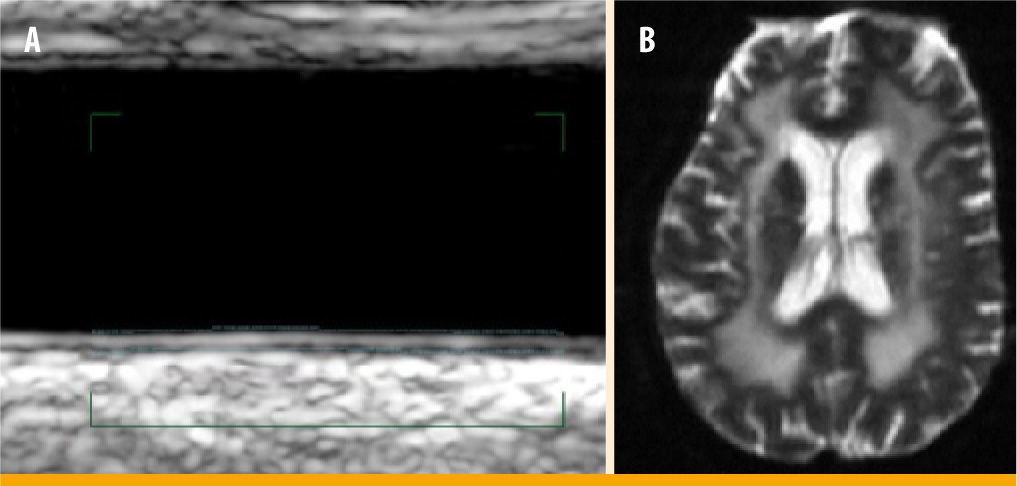

Marcadores pronósticos mediante técnicas de imagenEn los pacientes con diabetes, en ocasiones será útil recurrir a técnicas de imagen para seleccionar a aquellos de alto riesgo. En prevención primaria la técnica de elección son los ultrasonidos. Debido a su reproducibilidad y seguridad, permiten que sean aplicados a grandes grupos de población y ayudan en la estratificación y seguimiento. Tras un ictus o un AIT las técnicas de neuroimagen permiten valorar el grado de afectación vascular y, consecuentemente, el riesgo de recurrencia; de ahí su utilidad en prevención secundaria (figura 1).

La realización de una técnica de neuroimagen (TC o RM) es obligatoria en el diagnóstico de la enfermedad vascular cerebral (ictus o AIT). Una observación detallada de la prueba permitirá encontrar marcadores pronóstico que serán de gran utilidad a la hora de establecer el tratamiento de prevención en nuestro paciente.

Infartos silentes. Los infartos silentes, como su propio nombre indica, son lesiones isquémicas que no han tenido repercusión clínica. Generalmente son de tamaño pequeño y suelen localizarse en la sustancia blanca semioval o en la zona de los ganglios basales. Su presencia se asocia a los factores de riesgo vascular, en especial la hipertensión, y se han utilizado como marcadores pronóstico para el desarrollo de demencia vascular (riesgo a 5 años en mayores de 60 años del 52-82%) o incidencia de nuevos ictus (riesgo anual del 10%).

Leucoaraiosis. Es una palabra procedente del griego (leuko, blanco, y araios, rarefacción), acuñada por el neurólogo canadienses Vladimir Hachinski en 1987, que se utiliza para describir la pérdida difusa de densidad en la sustancia blanca y las áreas periventriculares. Aunque la causa de esta desmielinización no ha sido aclarada del todo, está directamente relacionada con factores de riesgo vascular (hipertensión, diabetes, edad) y su presencia es un potente factor pronóstico de riesgo de demencia y recurrencia vascular (2,8%/año)39.